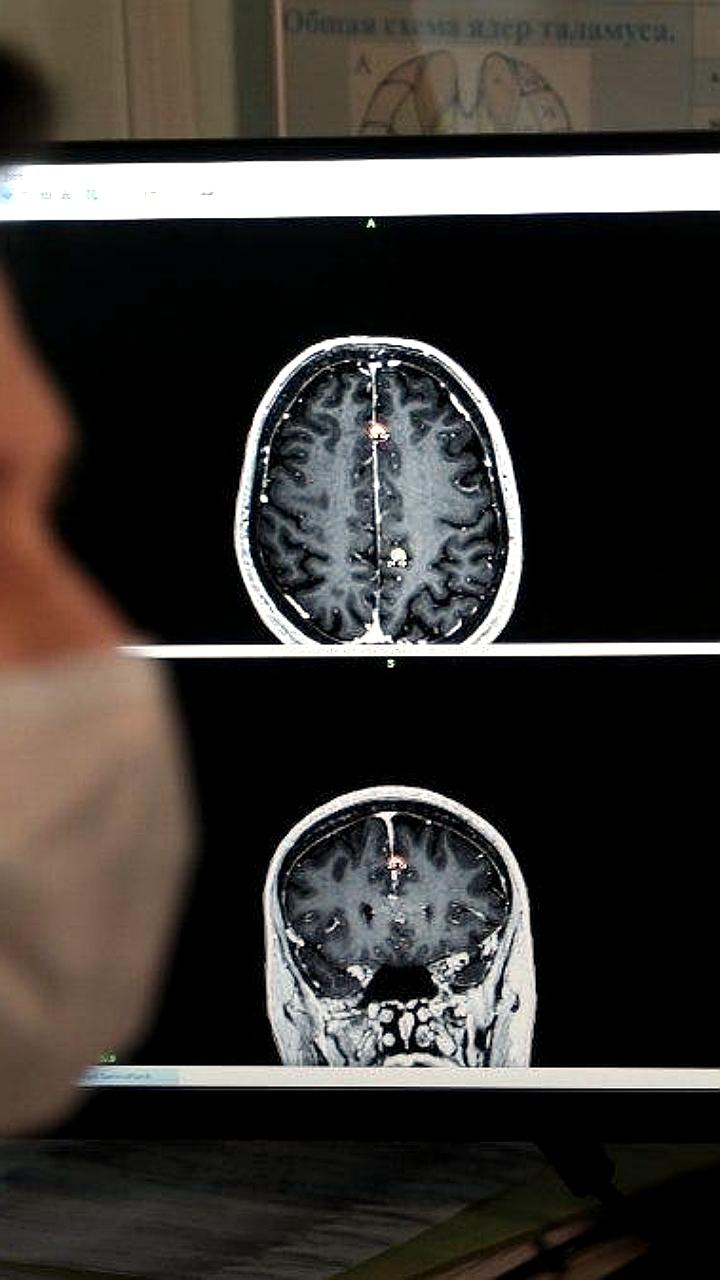

Президент Владимир Путин ознакомился с проектом иммунотерапии рака который ведет в научно технологическом университете Сириус ученый вернувшийся из США Встреча состоялась 9 сентября на федеральной территории Исследователь работает над методиками борьбы со злокачественными новообразованиями центральной нервной системы глиобластомой и глиомой Эти агрессивные формы онкологии приводят к смерти многих пациентов через 3 12 месяцев после диагностики Существующие сейчас методы паллиативные они могут лишь продлить жизнь на несколько месяцев пояснил специалист Подписывайтесь на Ъ Сочи

Президенту России Владимиру Путину рассказали о перспективных разработках молодых ученых в терапии агрессивных злокачественных новообразований центральной нервной системы Глава государства во вторник посетил лабораторный комплекс научно технологического университета Сириус который был открыт в сентябре 2022 года Руководитель научной группы научного центра трансляционной медицины университета Сириус Арсений Южалин сообщил президенту о проекте по иммунотерапии рака Молодой ученый отметил что их группа специализируется на исследованиях в области терапии злокачественных новообразований центральной нервной системы глиобластома глиома и так далее Он объяснил что это страшные заболевания с крайне низкими показателями выживаемости в среднем пациенты живут от трех до 12 месяцев после постановки диагноза при этом эффективного способа их лечения сейчас нет а существующие методы по большей части паллиативные Задача нашего молодежного проекта найти новые терапевтические стратегии для лечения таких видов рака В частности мы занимаемся иммуноонкологией пытаемся перепрофилировать иммунологически холодные опухоли в иммунологически горячие опухоли для того чтобы усилить проникновение иммунных клеток в опухоль и тем самым победить рак сказал Южалин Ученые ожидают что их разработки помогут улучшить прогноз онкологических пациентов добавил руководитель научной группы